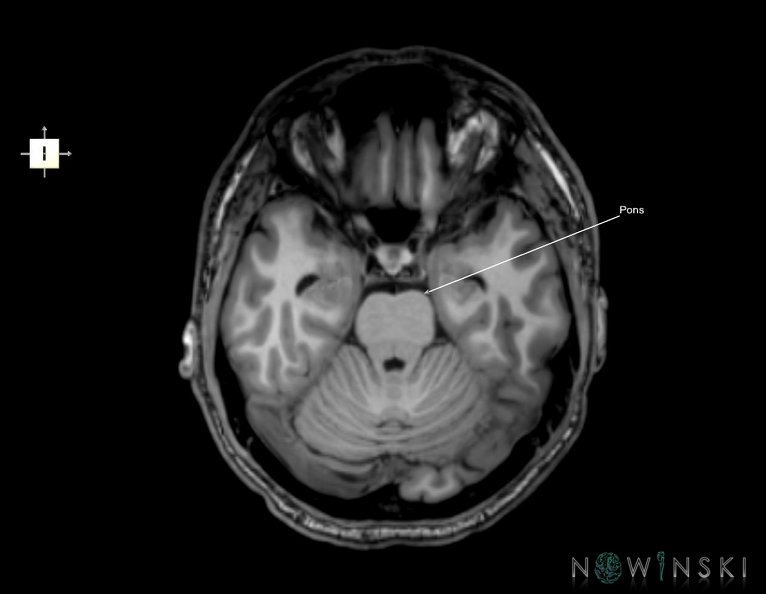

G6.T9.4.V6.P-20.Brainstem–Triplanar

G6T9.4.Brainstem–Triplanar

24